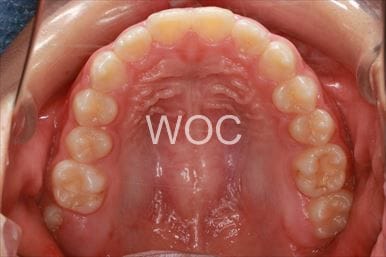

出っ歯舌側矯正

上下舌側矯正を希望。

通院状況や歯みがきの協力が良かったため、1年7ヶ月で治療を終えることができました。※装置と注意事項に関しては、大人の矯正装置一覧へ。

- 年齢:20歳女性

- 主訴:出っ歯が気になる

- 基本矯正料金:120万円

- 治療期間:1年7ヶ月

- 抜歯部位:上顎両側第一小臼歯